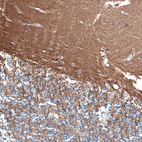

Immunohistochemical staining of human cerebellum shows moderate positivity in neuropil.